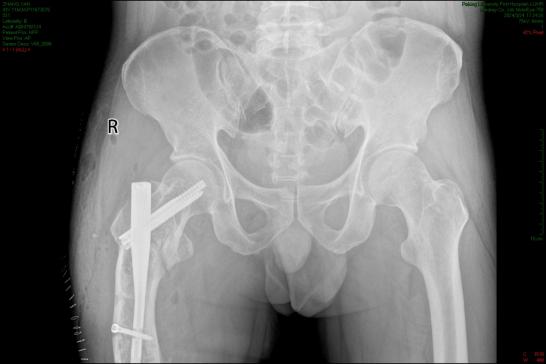

∩ω∩ 癌症“骨转移”就活不久了?警惕4大骨转部位早干预!也是许多癌症骨转移的高发部位。前列腺癌、乳腺癌、肺癌等癌症患者,骨转移时最容易发生于骨盆。骨盆部位的骨转移常表现为髋部或腹股沟疼痛,这种疼痛在行走或负重时会明显加剧,患者常常会误以为是普通的关节炎而延误治疗。更为严重的是,当癌细胞转移到骨盆时,骨质会变得脆...